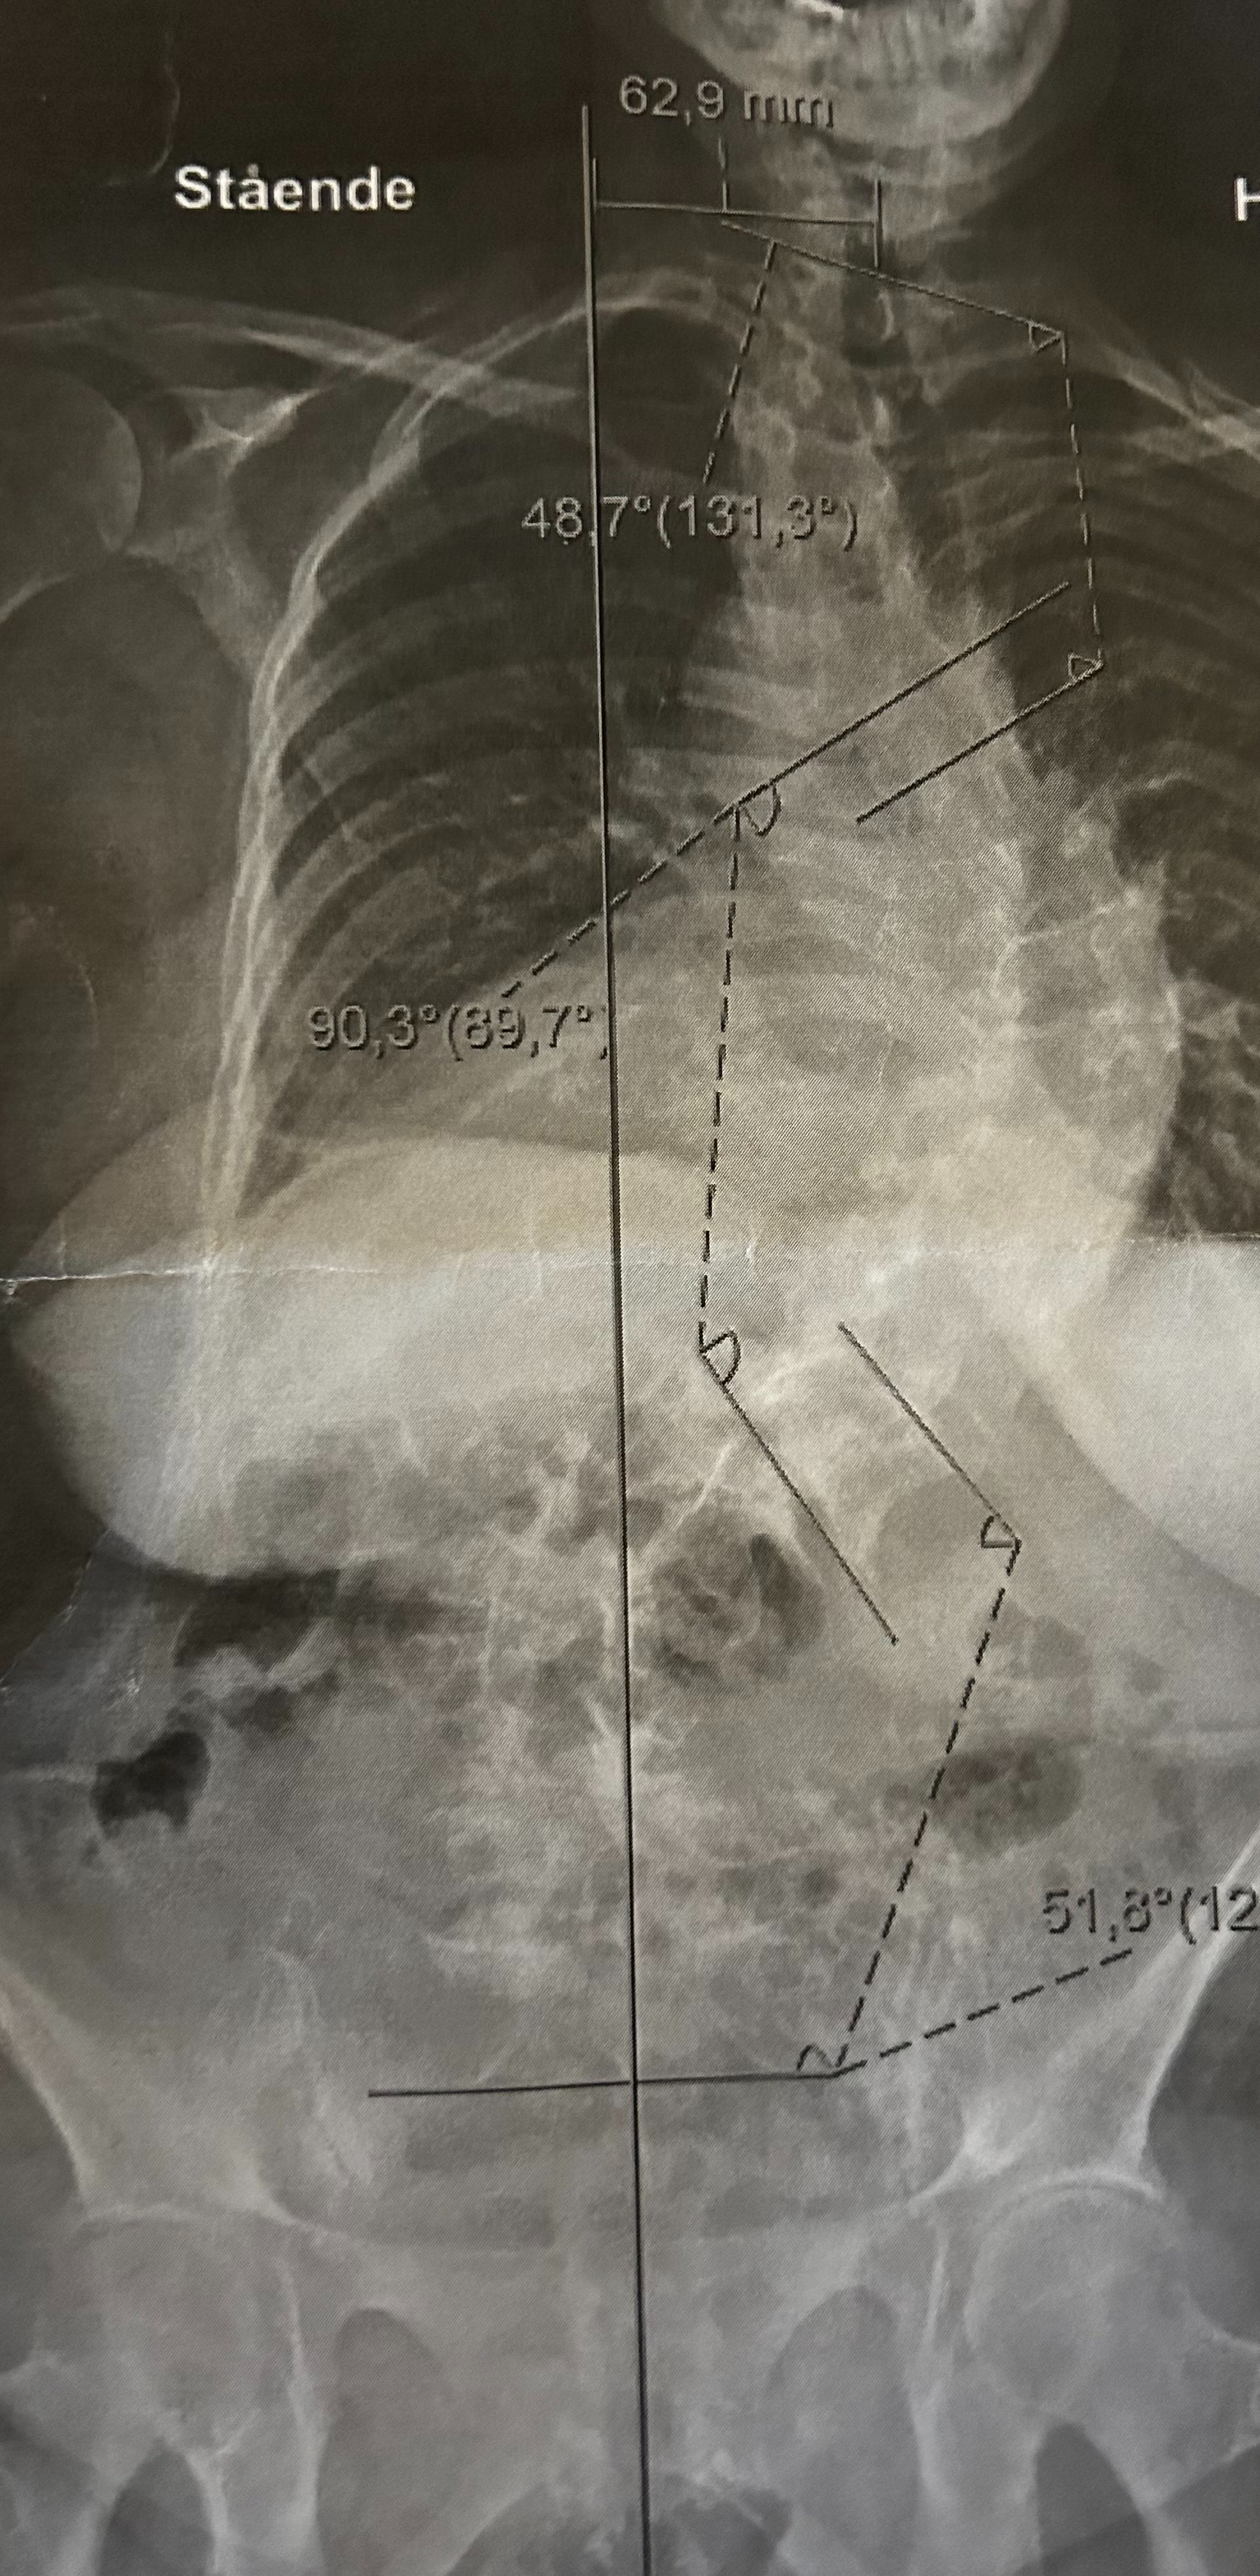

• Skoliosen: Som vist på bildet lider vår mor også av alvorlig idiopatisk skoliose. På bare tre år har ryggkrummingen hennes forverret seg fra 64 til 90 grader. Et helt sinnssykt fenomen. Som følge av dette er mulighetene for å bevege seg fritt blitt fryktelig begrenset. Hun er avhengig av krykke innendørs, og scooter for å bevege seg mer enn 30 meter utendørs. På grunn av alvorlig ME anses kirurgi i dag som for risikabelt (fare for at hun ikke kommer seg igjen, lammelse eller verre).

• The Scoliosis: As seen in the picture, our mother also suffers from extreme scoliosis. In just three years, her spine curvature worsened from 64 to 90 degrees. Because of her severe ME, surgery is currently deemed too risky (risk of paralysis or worse).